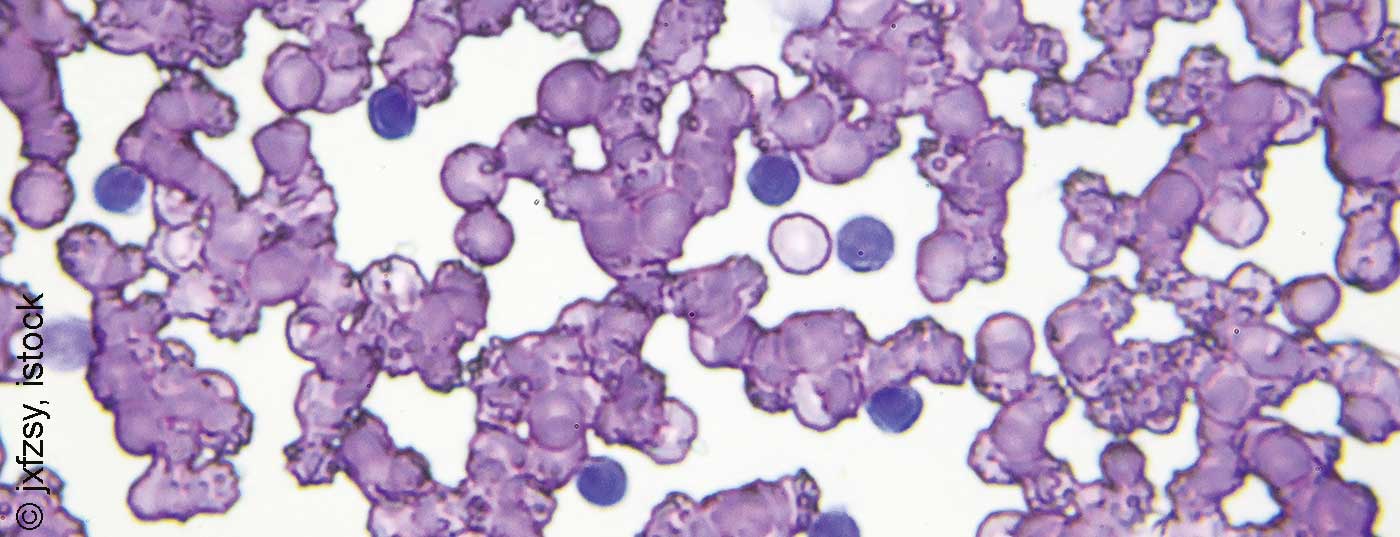

Valide prognostische und insbesondere prädiktive Marker können in der Behandlung von Krebserkrankungen eine entscheidende Rolle spielen. Mit der Entwicklung neuer therapeutischer Optionen zur Behandlung der chronischen lymphatischen Leukämie (CLL) befindet sich auch die Risikostratifizierung in stetem Wandel.